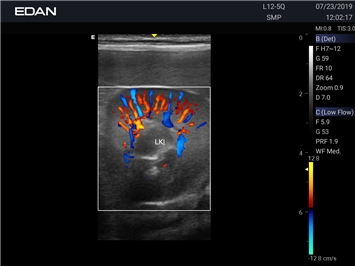

Да

Высокочастотный импульсный допплер:

Цветовой допплер:

Постоянно-волновой допплер:

Импульсно-волновой допплер: